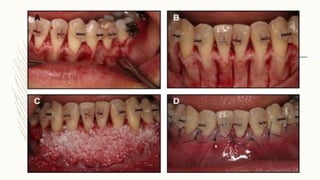

SURGICAL TECHNIQUE – STEP1 – FLAP DESIGN – Full thickness flap (most coronal aspect) + split thickness flap(apical portion) – Periosteal layer is removed – Access to alveolar bone – Mesial and distal extension

– STEP 2– DECORTICATION – Under LA using low speed no.2 carbide bur Vertical cortical incisions performed interproximally and extending well beyond dental apices – Subapical horizontal corticotomy given connecting interdental cuts – Done on both labial and lingual/palatal aspect of alveolar bone

– STEP 3– PARTICULATE BONE GRAFTING – Material – Deproteinised bovine bone, autogenous bone, DFDBA – Use of Platelet Rich Plasma/Calcium sulfate - Increases stability of graft – 0.25 to 0.5ml of graft material required per tooth

– STEP 4– CLOSURE OF FLAP – Sutures in the midline at interproximal areas followed by other areas by interrupted sutures